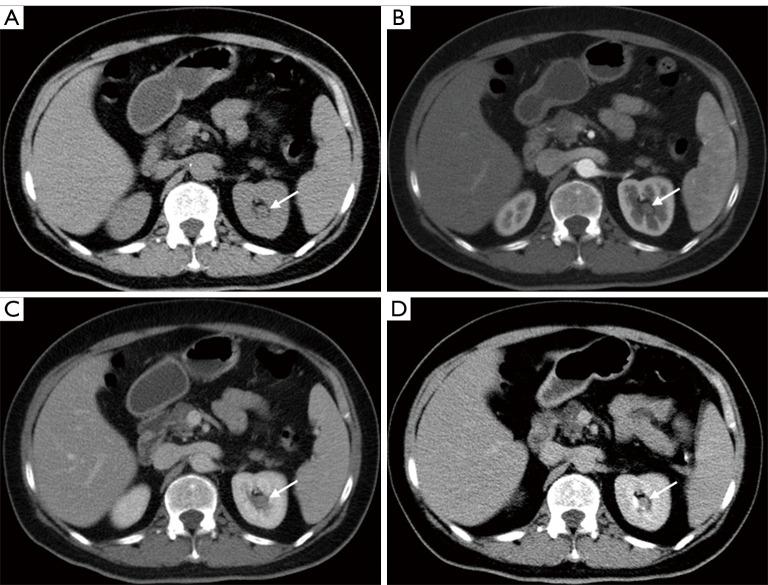

Nine cases of RPH were collected from 5 males and 4 females, aged 16-70 years old, with a median age of 41 years. Five cases were located in the left kidney and 4 cases were located in the right kidney. The clinical symptoms mostly presented with hematuria. Nine cases demonstrated solitary masses, with 4 cases with blurred margins and 5 cases with well-defined margins. The size of the mass was about 1.5-8.0 cm, and the median size was 2.5 cm. The US showed mostly hypoechoic masses and color Doppler flow imaging (CDFI) showed minimal to no blood flow signal. Unenhanced CT scans showed mostly hypodensity and mostly mild continuous enhancement on an enhanced scan. The intensity of lesions was commonly heterogeneous on MRI due to hemorrhage and necrosis. One case showed mild continuous enhancement on an enhanced MRI scan.

The imaging findings of RPH commonly present as a focal lesion with blurred or well-defined margins, mild and continuous enhancement, and no cachexia of the clinical symptoms. RPH should be differentiated from malignant tumors of the renal pelvis for treatment.